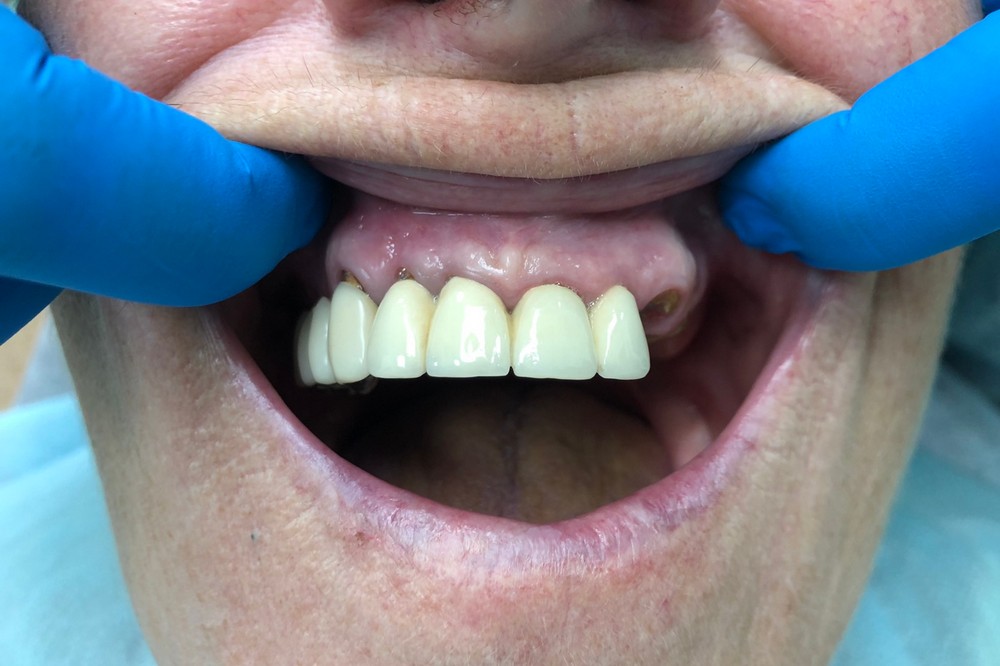

Был достигнут отличный результат, что подтверждается красивой улыбкой благодарной пациентки.